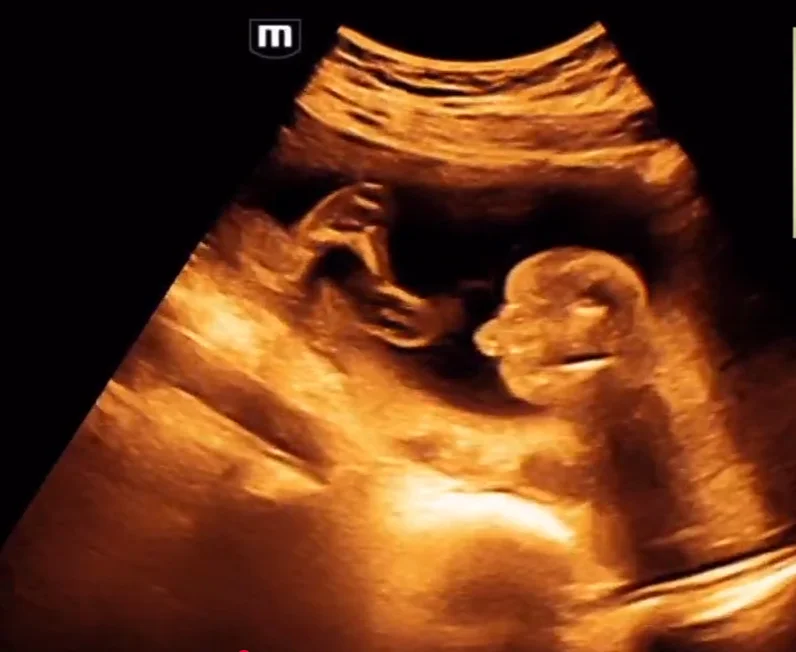

Cứng đa khớp bẩm sinh (Arthrogryposis Multiplex Congenita - AMC) / Chuỗi biến dạng do thai nhi bất động/giảm động (Fetal Akinesia/Hypokinesia Deformation Sequence - FA(H)DS)